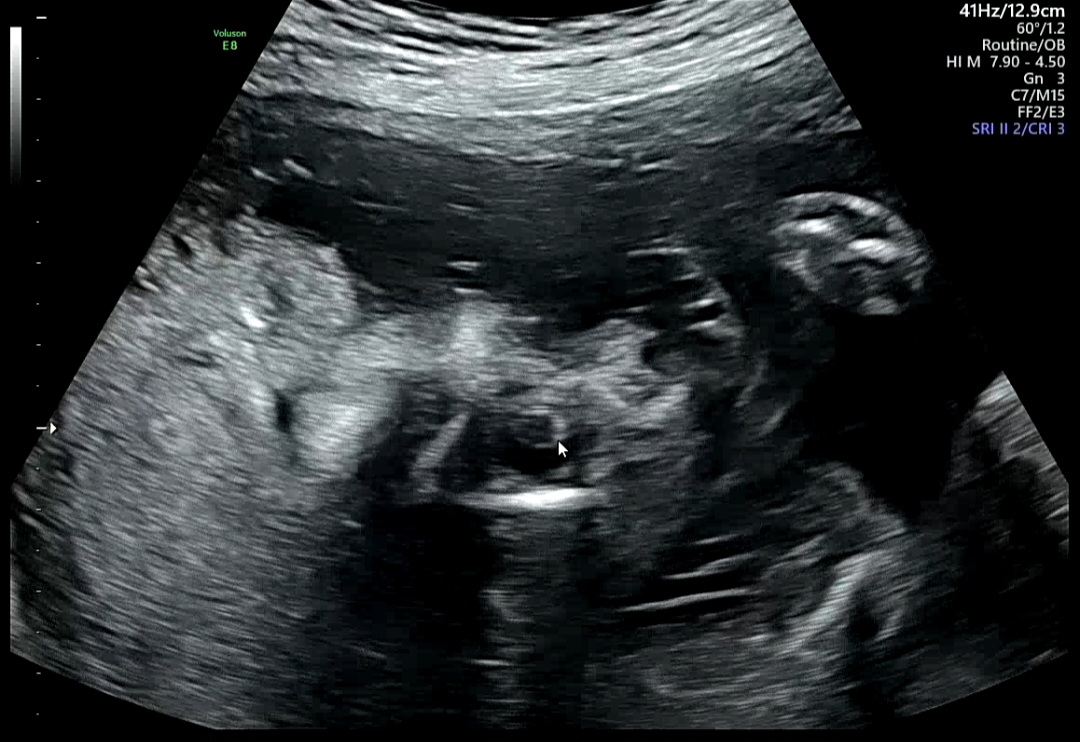

2. 심장 구조 확인 (4CV,3V, IVS, A-A, LV OT, RV OT)

1) 4CV (Four Chamber View, 4심방 단면)

심장의 4개 방(좌·우심방, 좌·우심실) 이 한눈에 보이는 장면

→ 좌우 크기가 균형 있고 벽이 잘 구분되면 정상

2) 3V (Three Vessel View, 3혈관 단면)

심장에서 나오는 세 가지 주요 혈관(폐동맥, 대동맥, 상대정맥)을 함께 보는 단면

→ 세 혈관이 일정한 크기로 잘 배열되어 있다면 정상 혈관 구조

3) IVS (Interventricular Septum, 심실중격)

IVS : 좌심실과 우심실 사이 벽(중격)을 뜻함

→ 이 부분에 구멍이 있으면 심실중격결손(VSD)이라고 하는데,

위 사진처럼 중격이 잘 보이고 화살표로 표시된 부분에 단절 없이 이어져 있다면 정상

4) A-A (Aortic Arch, 대동맥궁)

A-A : 대동맥궁은 심장에서 나와 온몸으로 혈액을 보내는 중요한 통로

→ 활처럼 휘어지는 모습이 잘 보이면 정상적으로 형성된 것을 의미

5) LVOT / RVOT

LVOT (Left Ventricular Outflow Tract)

→ '좌심실 유출로', 좌심실에서 대동맥(Aorta)으로 피가 나가는 통로

혈류가 한쪽 방향으로 잘 흐르는지, 대동맥이 제대로 연결되어 있는지 확인

RVOT (Right Ventricular Outflow Tract)

→ '우심실 유출로', 우심실에서 폐동맥(Pulmonary artery)으로 피가 나가는 통로

폐동맥이 정상적으로 심장에서 나오는지 확인